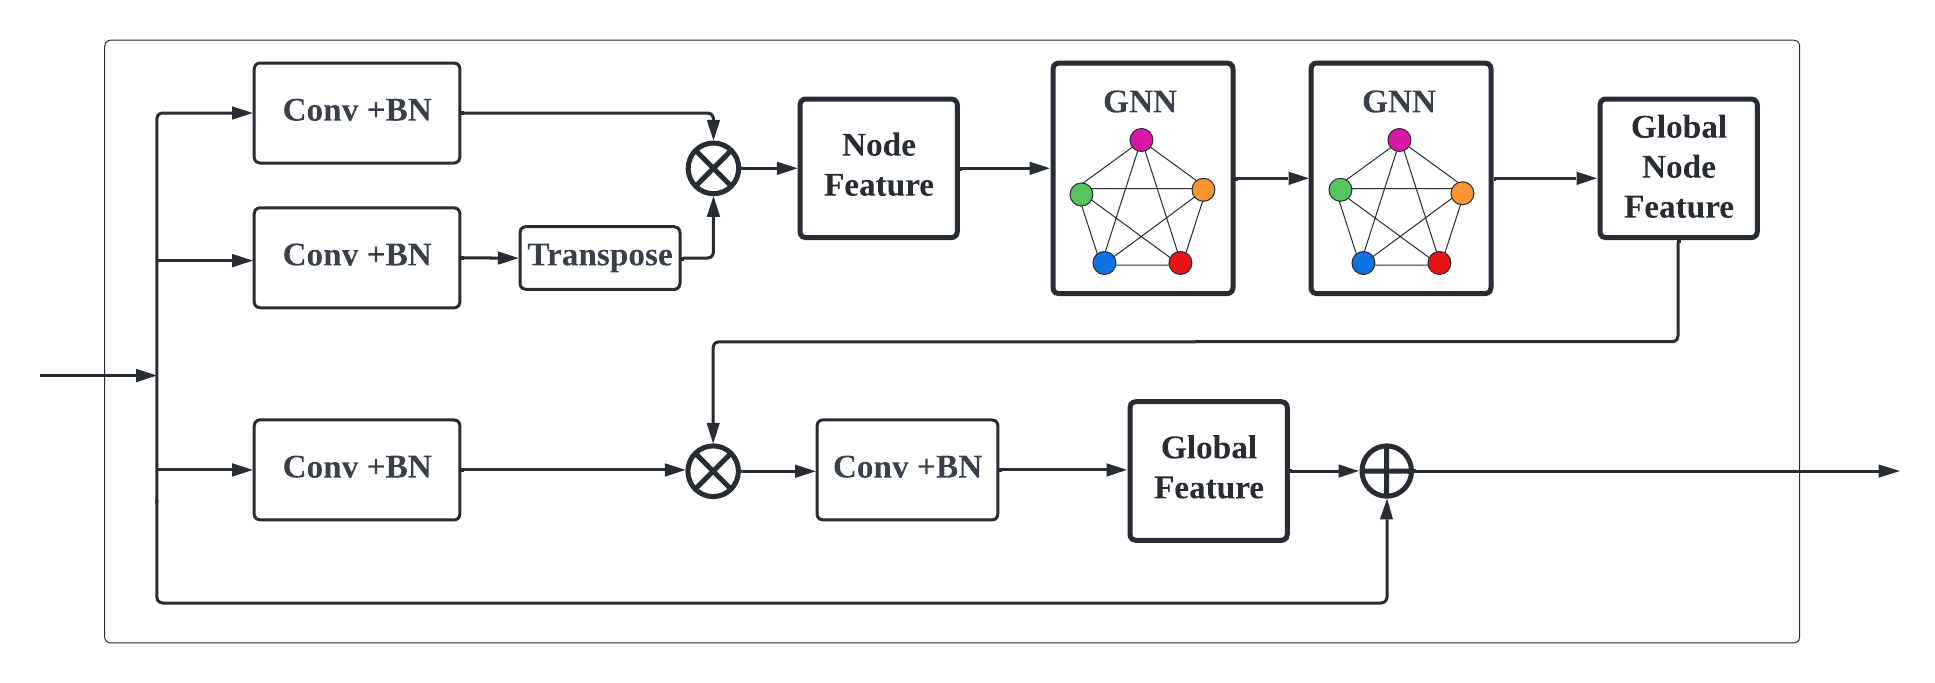

The bridge module is added to the skip connection from the original U-Net [22] with a GCN transformation (seen in Fig. 5).

It bridges the encoder with ETB and the decoder constructed by convolutions to maximize the advantages brought by transformers and convolutions. It is capable of promoting the optimization of local features and generalization across data from different domains.

GCN in Fig. 5 (see detail structure in Fig. 7) is to extract the spatial features of topological graphs by using the topologically-stable relationship information. Meanwhile, after convolutional graph operation, pixels feature belonging to the same class in semantic segmentation will be close to each other in the feature manifold (see Fig. 6).

We multiplied the feature map with the corresponding transpose as input of the GCN block. Global features will be generated by two layers of GCN blocks (see Fig. 7), while the global topological relationship of graph structure-based features (see Fig. 6) is obtained. The final feature map is fused by adding (see Fig. 5) the encoder output and the global relationship node feature together.